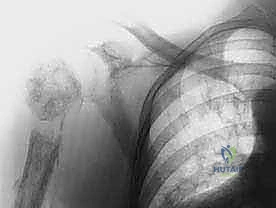

في جراحة استئصال الربع الأمامي التقليدية، يقوم الجراح بإزالة:

1. الطرف العلوي بالكامل: الذراع، الساعد، واليد.

2. لوح الكتف (Scapula): العظمة المثلثة الكبيرة في الظهر.

3. عظم الترقوة (Clavicle): يتم إزالة جزء منها أو إزالتها بالكامل، وهي العظمة التي تربط الكتف بعظم القص.

4. العضلات المحيطة: العضلات التي تربط هذه العظام بالقفص الصدري.

الخطوة 6: استئصال الورم والطرف (En Bloc Resection)

بمجرد تحرير جميع التوصيلات العظمية والعضلية والوعائية، يتم إزالة الطرف العلوي بأكمله مع الكتف والورم ككتلة واحدة، دون اختراق كبسولة الورم لضمان عدم تسرب الخلايا السرطانية.